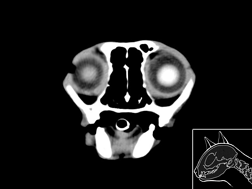

Atlas cérébral du chat SCTM

Scanner tissu mou

>> 18 coupes

Atlas cérébral du chat SCTO

Scanner tissu osseux

>> 18 coupes